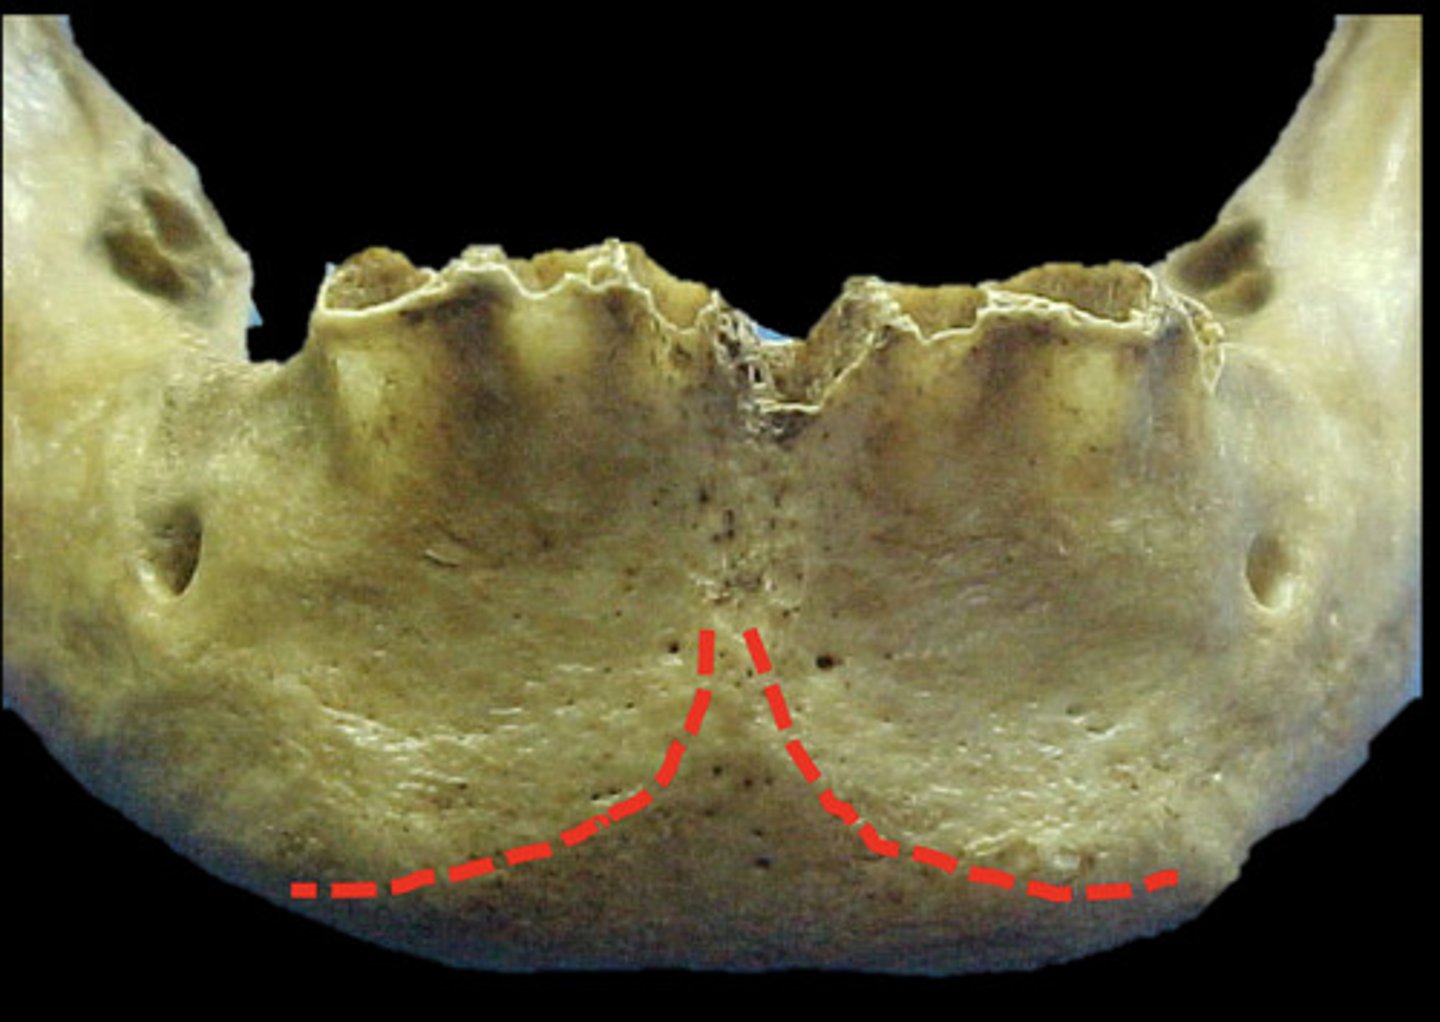

mental ridge?

What does the mental ridge look like radiographically?

information on mental ridge

radiopaque & found in the mandible